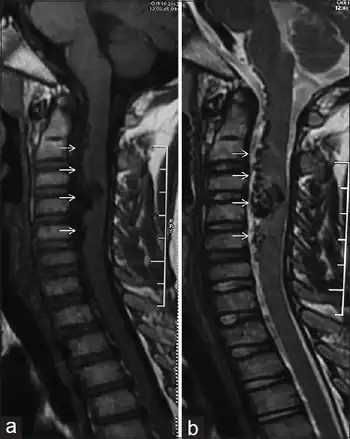

| a,b) Spinal arteriovenous malformation | |

Spinal arteriovenous malformations

Spinal arteriovenous malformations (AVMs, or angiomatous malformations) are congenital (from birth) abnormalities of blood vessels. Arteries that directly communicate with veins bypass the capillary network (which has not yet developed) and thus creates a shunt. AVMs appear as a mass of convoluted, dilated vessels. In regards to the spinal cord, they are usually located in the thoracolumbar region (between the thoracic and lumbar regions, 60% of the time), as opposed to the upper thoracic (20%) and cervical regions (approximately 15%). Cervical malformations arise from the anterior spinal artery and lie within the cord, whereas thoracolumbar malformations can be internal, external or encompass both areas of the cord.[3]

Myelography is used to confirm the diagnosis of AVMs and it shows 'snake-like' vessels on the cord's surface. If the myelogram is positive, angiography is required to show the extent of malformation and the exact site of the shunt. Magnetic resonance imaging (MRI) may show the appropriate area. If AVMs are left untreated, 50% of patients with gradual symptoms will be unable to walk within 3 years of onset. Surgical occlusion has been shown to halt the progression and may improve any gait or incontinence.[3][6]